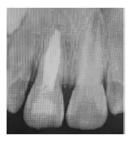

X線片示:11根管短小且粗大,根尖孔未閉合,管壁呈平行狀,根中1/3見內(nèi)吸收,牙根發(fā)育7期,根部未見根折線,根尖周有稀疏區(qū);21根部發(fā)育程度與11相同,根部未見根折線及內(nèi)外吸收,根尖周未見明顯稀疏區(qū)(圖1a)。

圖1a 術前X線片